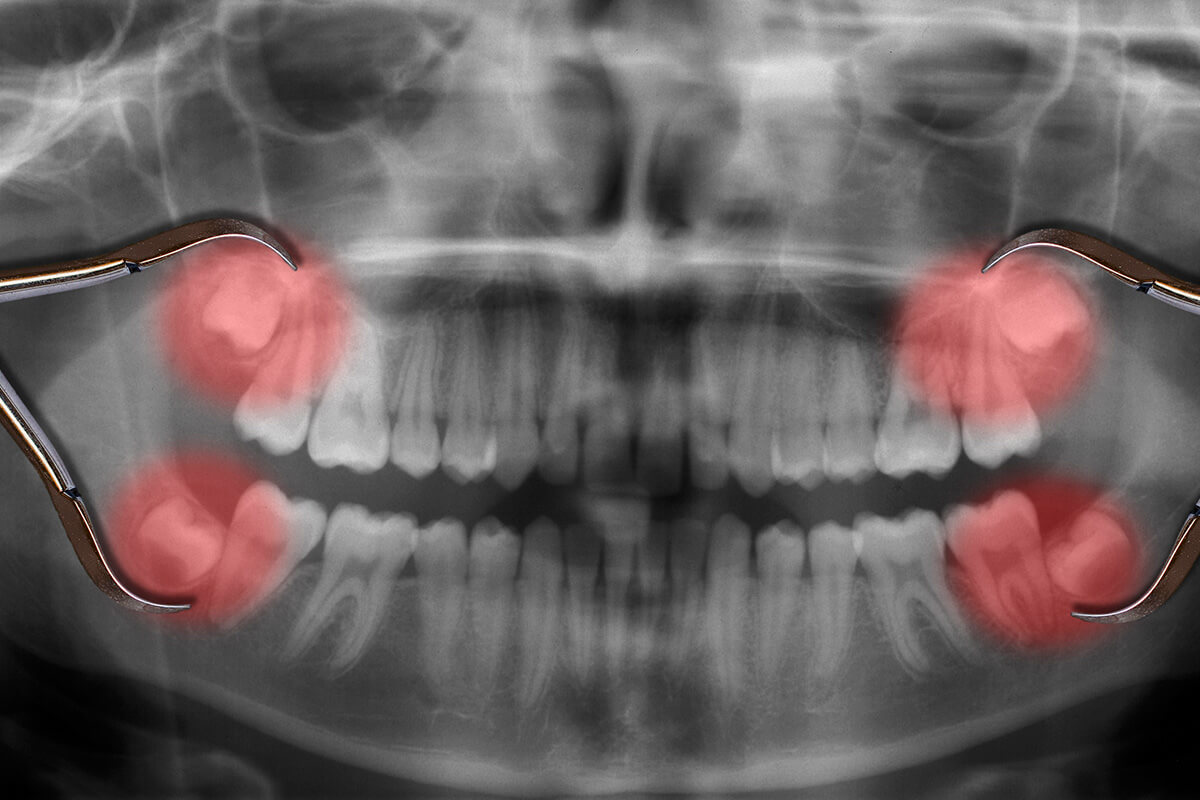

Wisdom teeth removal is a common surgical procedure to extract the third molars, which usually emerge between the ages of 17 and 25. Many people experience pain, swelling, or infection due to impacted wisdom teeth, where the tooth doesn’t fully erupt. Overcrowding and misalignment of teeth can also result. The procedure typically involves local anaesthesia, and recovery includes managing swelling and discomfort. Post-surgery care includes rest, soft foods, and avoiding smoking. While not always necessary, removing wisdom teeth can prevent future complications, such as infections, gum disease, and damage to neighbouring teeth. Wisdom Teeth Removal:

- Reduces Infection Risk: Impacted or partially erupted wisdom teeth are prone to gum infections and decay. Extraction helps prevent painful infections like pericoronitis.

- Avoids Cysts and Tumors: Cysts or tumors can form around impacted wisdom teeth, damaging the jawbone and neighboring teeth. Early removal reduces this risk.

- Prevents Jaw Damage: Impacted wisdom teeth can damage the jaw and surrounding nerves. Removing them minimizes the risk of long-term bone and nerve damage.